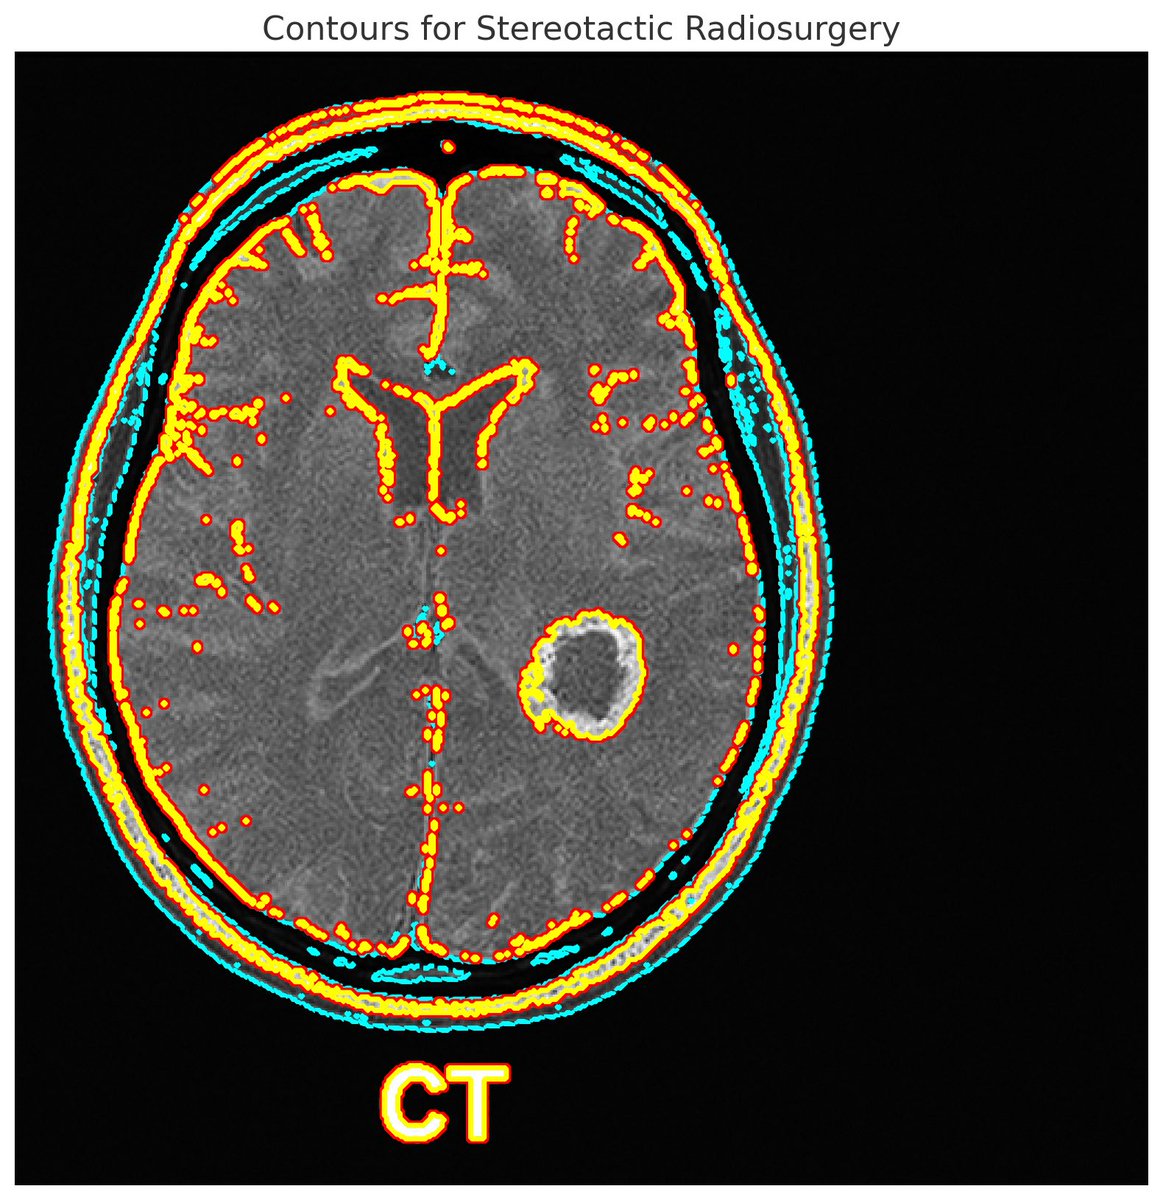

Excited to share our publication in @TheLancetOncol on the primary results from the UNITED study: a new paradigm in radiotherapy for patients with glioblastoma /1 @Sunnybrook @UofTDRO thelancet.com/journals/lanon…